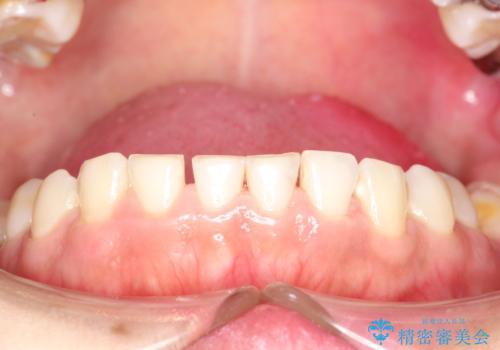

治療途中

かなり久しぶりの歯科医院との事で、全体的に古くからの歯垢・歯石が多く付着していたため、自費クリーニング(PMTC)60分コース・歯周ポケット検査(保険適応)を行いました。